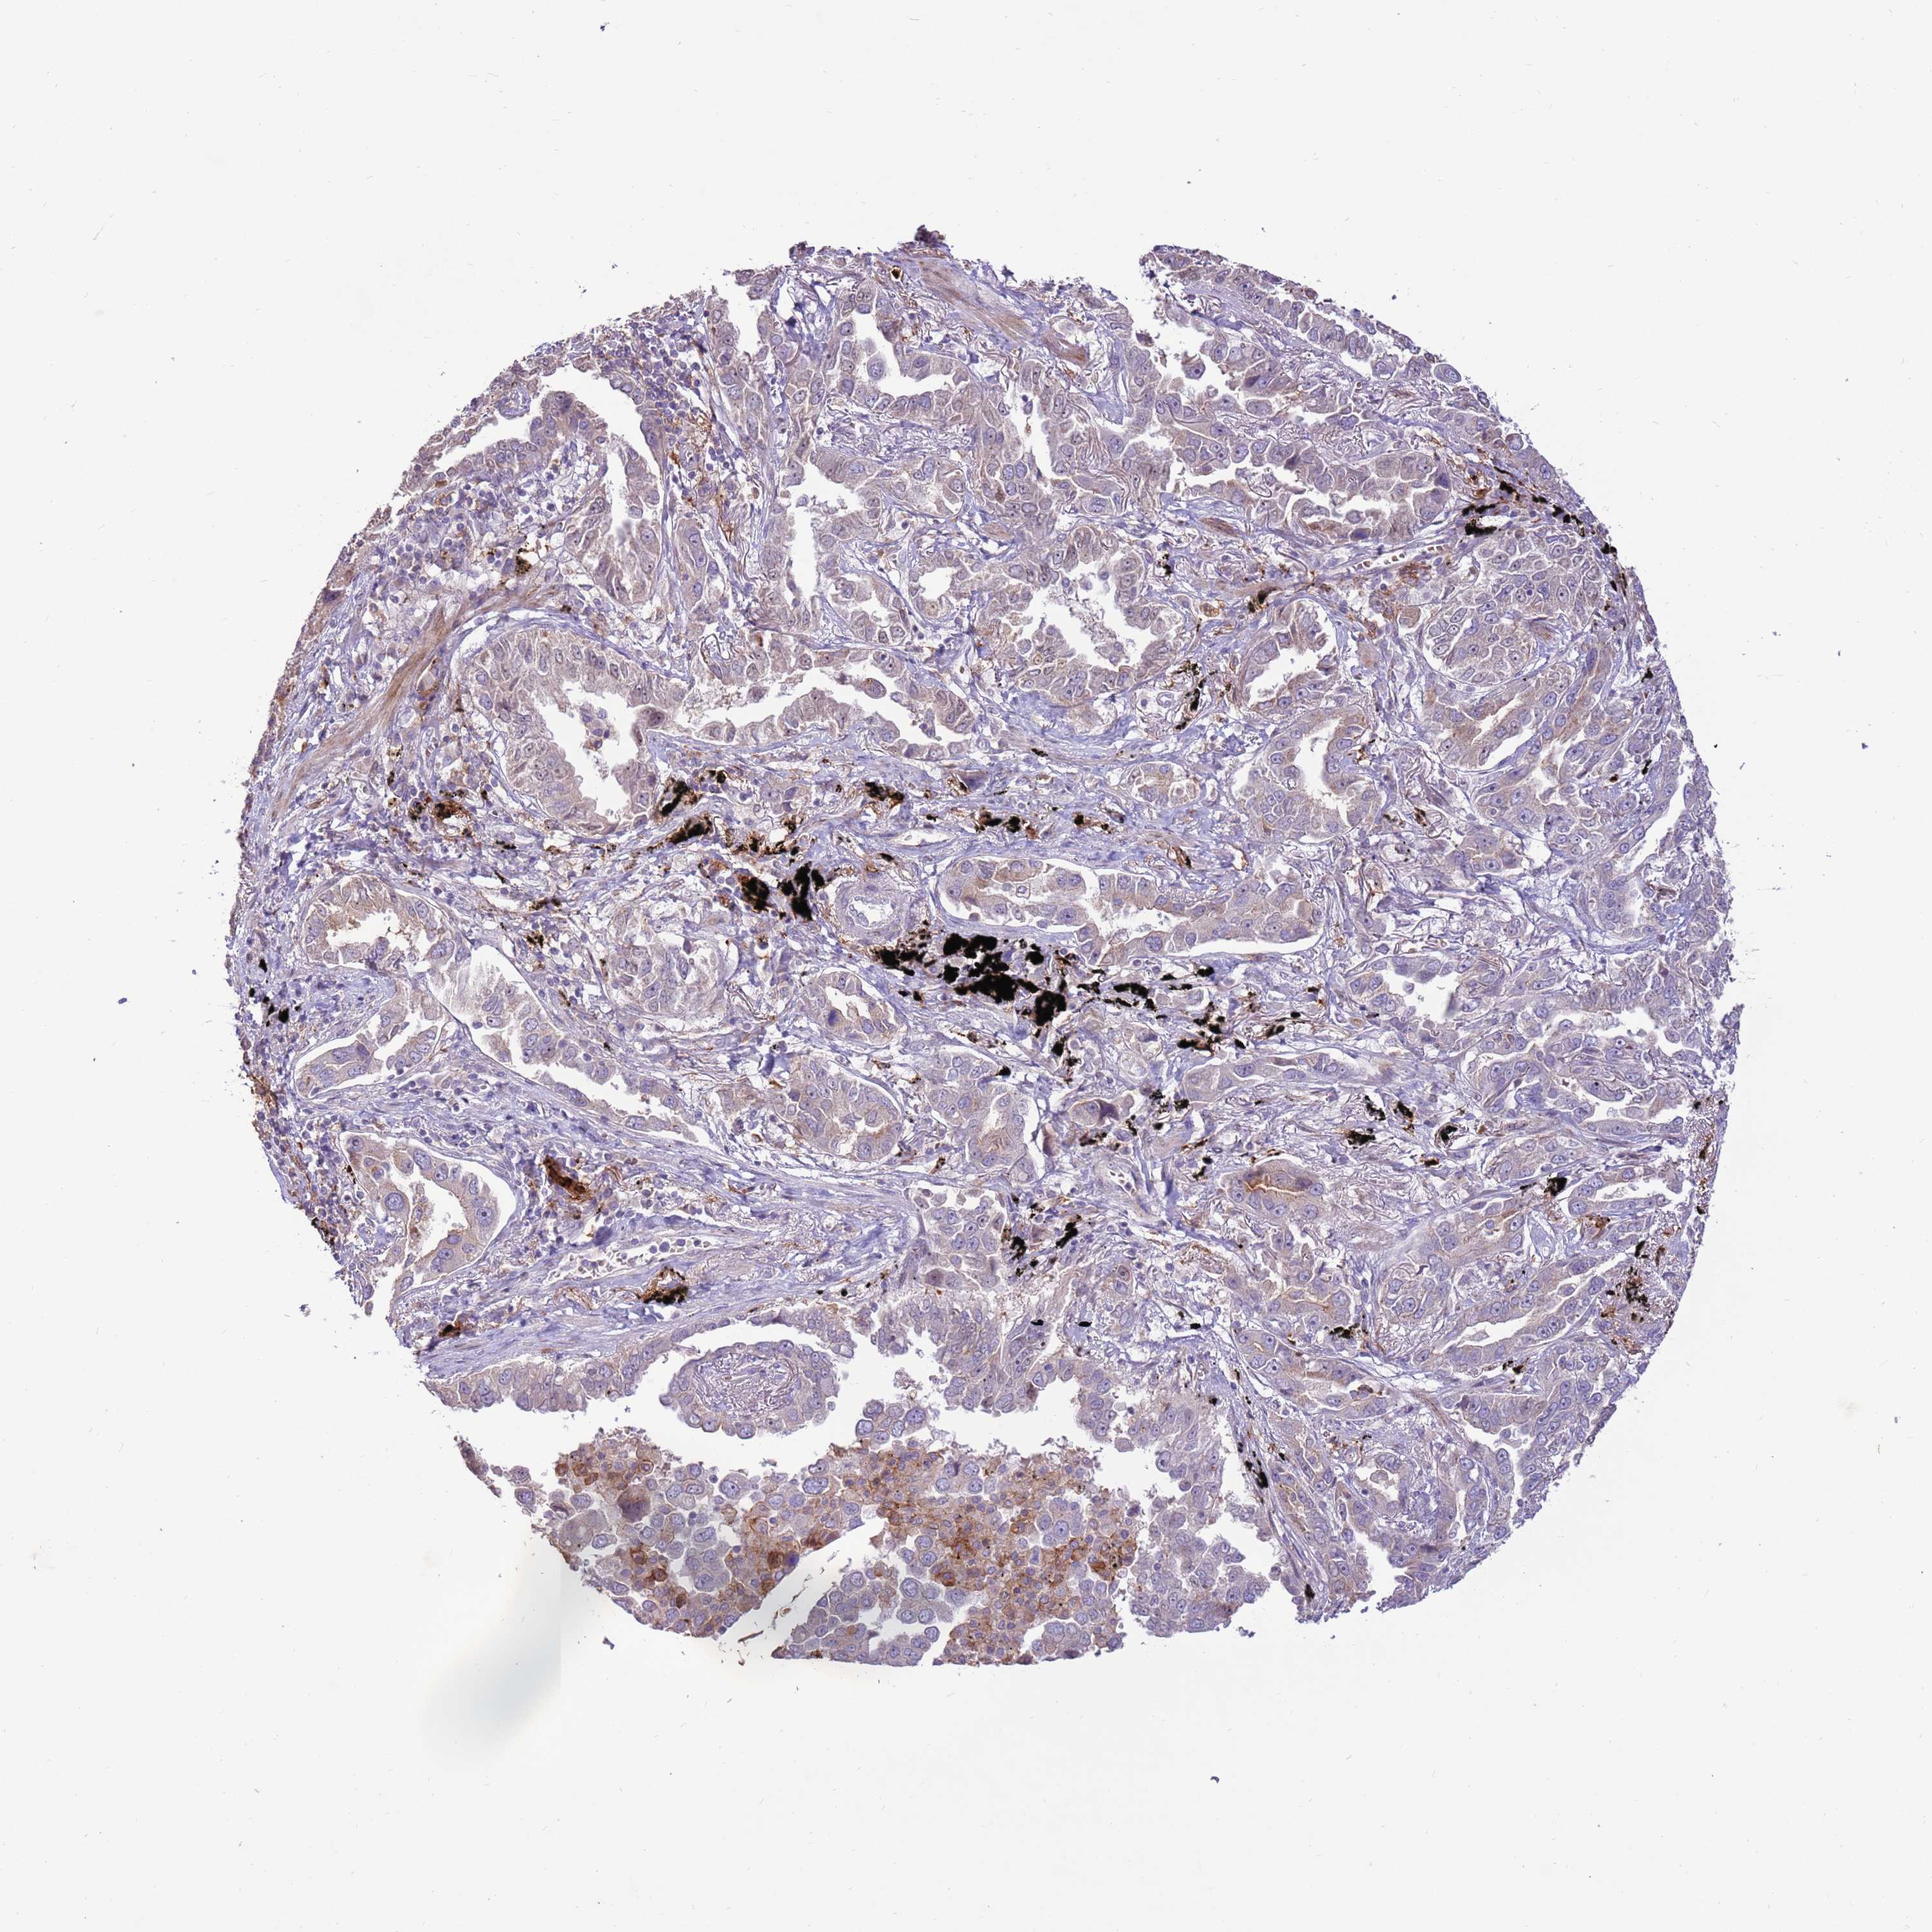

LUNG ADENOCARCINOMA (TCGA) - Interactive survival scatter ploti

The Survival Scatter plot shows the clinical status (i.e. dead or alive) for all individuals in the patient cohort, based on the same data that underlies the corresponding Kaplan-Meier plots. Patients that are alive at last time for follow-up are shown in blue and patients who have died during the study are shown in red.

The x-axis shows the expression levels (FPKM) of the investigated gene in the tumor tissue at the time of diagnosis. The y-axis shows the follow-up time after diagnosis (years). Both axes are complimented with kernel density curves demonstrating the data density over the axes. The top density plot shows the expression levels (FPKM) distribution among dead (red) and alive patients (blue). The right density plot shows the data density of the survived years of dead patients with high and low expression levels respectively, stratified using the cutoff indicated by the vertical dashed line through the Survival Scatter plot. This cutoff is automatically defined based on the FPKM cutoff that minimizes the p-score. The cutoff can be changed by dragging the vertical line or by entering a cutoff value in the square labeled "Current cut-off".

Under the Survival Scatter plot the p-score landscape (black curve; left axis) is shown together with dead median separation (red curve; right axis). Dead median separation is the difference in median mRNA expression between patients who have died with high and low expression, respectively. It is calculated as follows: median FPKM expression of dead patients with high expression - median FPKM expression of dead patients with low expression. This is intended to aid the user in visually exploring custom cutoffs and the associated p-scores and dead median separation.

Individual patient data is displayed and can be filtered by clicking on one or more of the category buttons on the top of the page. Categories describing expression level and patient information include: high, low, alive, dead, female, male and tumor stages. The scale of the x-axis can be toggled between linear and log-scale by clicking on the "x log" button. Mouse-over function shows TCGA ID, patient information and mRNA expression (FPKM) for each patient.

& Survival analysisi

Kaplan-Meier plots summarize results from analysis of correlation between mRNA expression level and patient survival. Patients were divided based on level of expression into one of the two groups "low" (under cut off) or "high" (over cut off). X-axis shows time for survival (years) and y-axis shows the probability of survival, where 1.0 corresponds to 100 percent.

LGI4 is not prognostic in Lung Adenocarcinoma (TCGA)